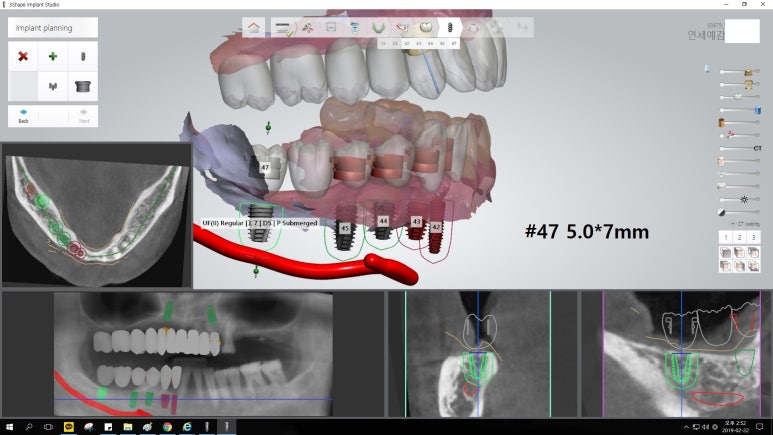

오늘은 임플란트, 조금 더 안아프고 간편하게 할 수 있는 방법에 대해

실제 저희 치과에서 진행한 사례를 통해 알아보고자 합니다.

50대의 나이에도 남은 이가 거의 없는 분입니다.

(아래 쪽은 원래 계획대로 진행되어 임플란트5개를 식립하였으며, 위 쪽은 환자가 도중에 2개의 임플란트만 심고 싶어하여 2개의 임플란트 식립)

이러한 세세한 시뮬레이션, ct를 이용한 컴퓨터 분석을 통해

더 정확하고 안전하게 적절한 위치에 임플란트를 식립할 수 있었으며

절개가 없는 비절개 방식을 이용한 인플란트로

수술시간이 짧고 실밥을 풀 필요가 없으며, 환자분의 만족도도 높습니다.